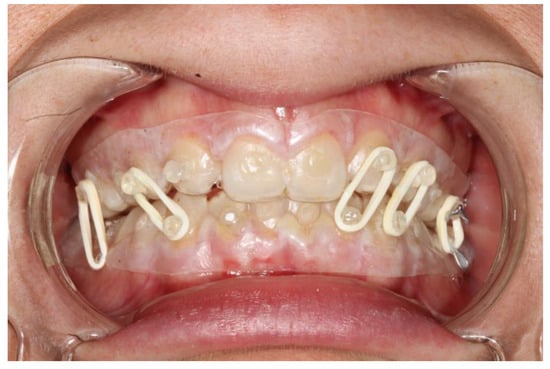

Figure 5. Intraoral view of patient 2 during the treatment; is it possible to note the slight problem with oral hygiene, which is nonetheless completely acceptable.

Figure 6. Intraoral view of patient 1 during the treatment; is it possible to note the slight problem with oral hygiene, which is nonetheless completely acceptable.

The fixation strength of the intermaxillary fixation was considered adequate in both cases (Figure 5 and Figure 6).

Occlusion and periodontal tissue were within normal clinical ranges after the treatment (Figure 6).

Only in the first patient, where the splint margin covered the attached gingiva, was some periodontal inflammation noted (Figure 7).